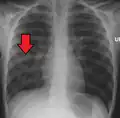

![]() | |

| Chest X-ray of a pneumonia caused by influenza and Haemophilus influenzae, with patchy consolidations, mainly in the right upper lobe (arrow) | |

A chest radiograph is frequently used in diagnosis.[23] In people with mild disease, imaging is needed only in those with potential complications, those not having improved with treatment, or those in which the cause is uncertain.[23][69] If a person is sufficiently sick to require hospitalization, a chest radiograph is recommended.[69] Findings do not always match the severity of disease and do not reliably separate between bacterial and viral infection.[23]

X-ray presentations of pneumonia may be classified as lobar pneumonia, bronchopneumonia, lobular pneumonia, and interstitial pneumonia.[75] Bacterial, community-acquired pneumonia classically show lung consolidation of one lung segmental lobe, which is known as lobar pneumonia.[42] However, findings may vary, and other patterns are common in other types of pneumonia.[42] Aspiration pneumonia may present with bilateral opacities primarily in the bases of the lungs and on the right side.[42] Radiographs of viral pneumonia may appear normal, appear hyper-inflated, have bilateral patchy areas, or present similar to bacterial pneumonia with lobar consolidation.[42] Radiologic findings may not be present in the early stages of the disease, especially in the presence of dehydration, or may be difficult to interpret in the obese or those with a history of lung disease.[24] Complications such as pleural effusion may also be found on chest radiographs. Laterolateral chest radiographs can increase the diagnostic accuracy of lung consolidation and pleural effusion.[41]